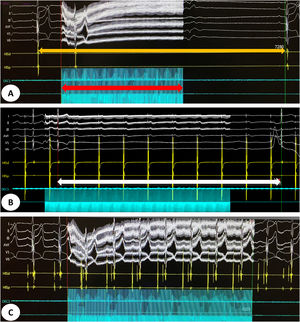

Detailed characteristics of the procedures are presented in Table 2. The mean procedure and fluoroscopy times were 115±30 min and 8.8±5.1 min, respectively. A positive mixed vagal response with extracardiac vagal stimulation was seen in all patients (asystole, and atrioventricular block when performing atrial pacing during vagal stimulation). The acute endpoint of the procedure (inhibition of vagal response after GP ablation) was achieved in all patients. Figure 2 shows an example of an initial mixed sinus and AV nodal vagal response and the result after successful CNA.

(A) Intracardiac electrogram showing a sinus pause of 7.28 s (orange arrow) induced by vagal stimulation for 4 s (red arrow) before cardioneuroablation. (B) Intracardiac electrogram showing an atrioventricular block (white arrow) induced by vagal stimulation during atrial pacing. (C) Intracardiac electrogram showing abolition of vagal response after cardioneuroablation.